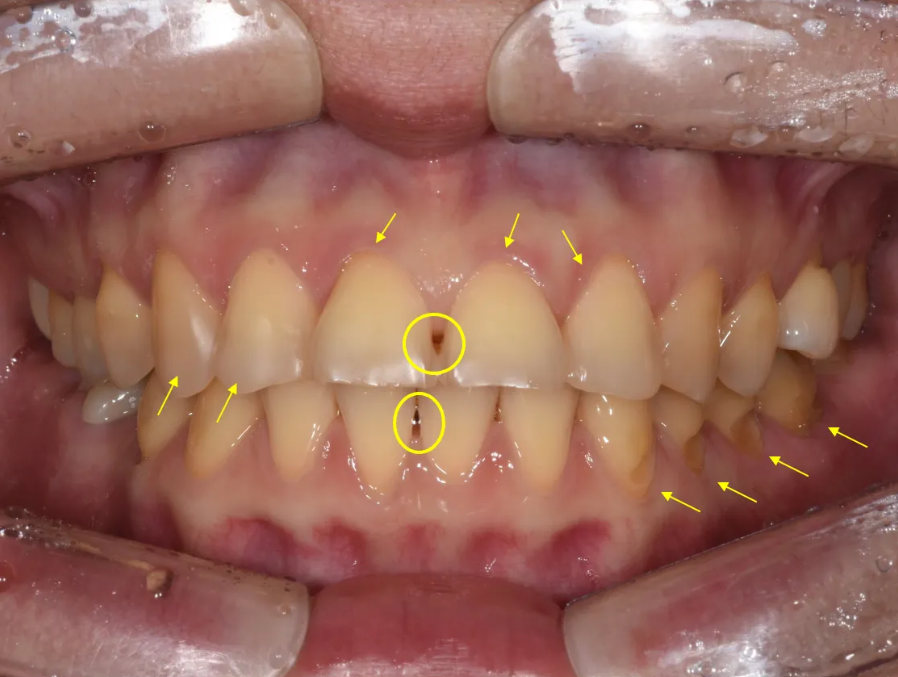

초진 구내 분석 – 다양한 문제점 확인

이제 본격적으로 입 안 상태를 자세히 살펴보겠습니다. 구내사진을 통해 확인된 문제점이 상당히 많았습니다.

윗니 앞니 부분의 문제점

레진 수복 흔적, 색상 문제, 치아 사이 검은 삼각형, 잇몸 비대칭

가장 눈에 띄는 문제는 앞면이 레진으로 수복되어 있는 상태였습니다. 아무래도 보기에 깔끔하지가 못하였고, 치아 전체적으로도 누런 색상(Yellowish)이 심했습니다. 또한 아래위 모두 앞니 사이에 뚫린 공간이 보였고("블랙 트라이앵글"), 뿌리쪽 부분이 심하게 파여 있었어요. 잇몸의 위치도 좌우가 비대칭적이었습니다.

아래에서 보니 아래위 앞니가 상당히 긴밀하게 물리고 있었습니다.

또한 가운데 앞니 두 개가 앞으로 돌출되어 있었는데, 특히 바깥쪽이 더 밖으로 나오면서 소위 '나비이빨' 형태를 보이고 있었습니다.

가운데 앞니 두 개와 왼쪽 옆 앞니의 잇몸 라인도 불균형하여 비심미적이었고, 가운데 앞니 사이에는 검은 삼각형(Black Triangle)이라 불리는 빈 공간이 보였습니다.